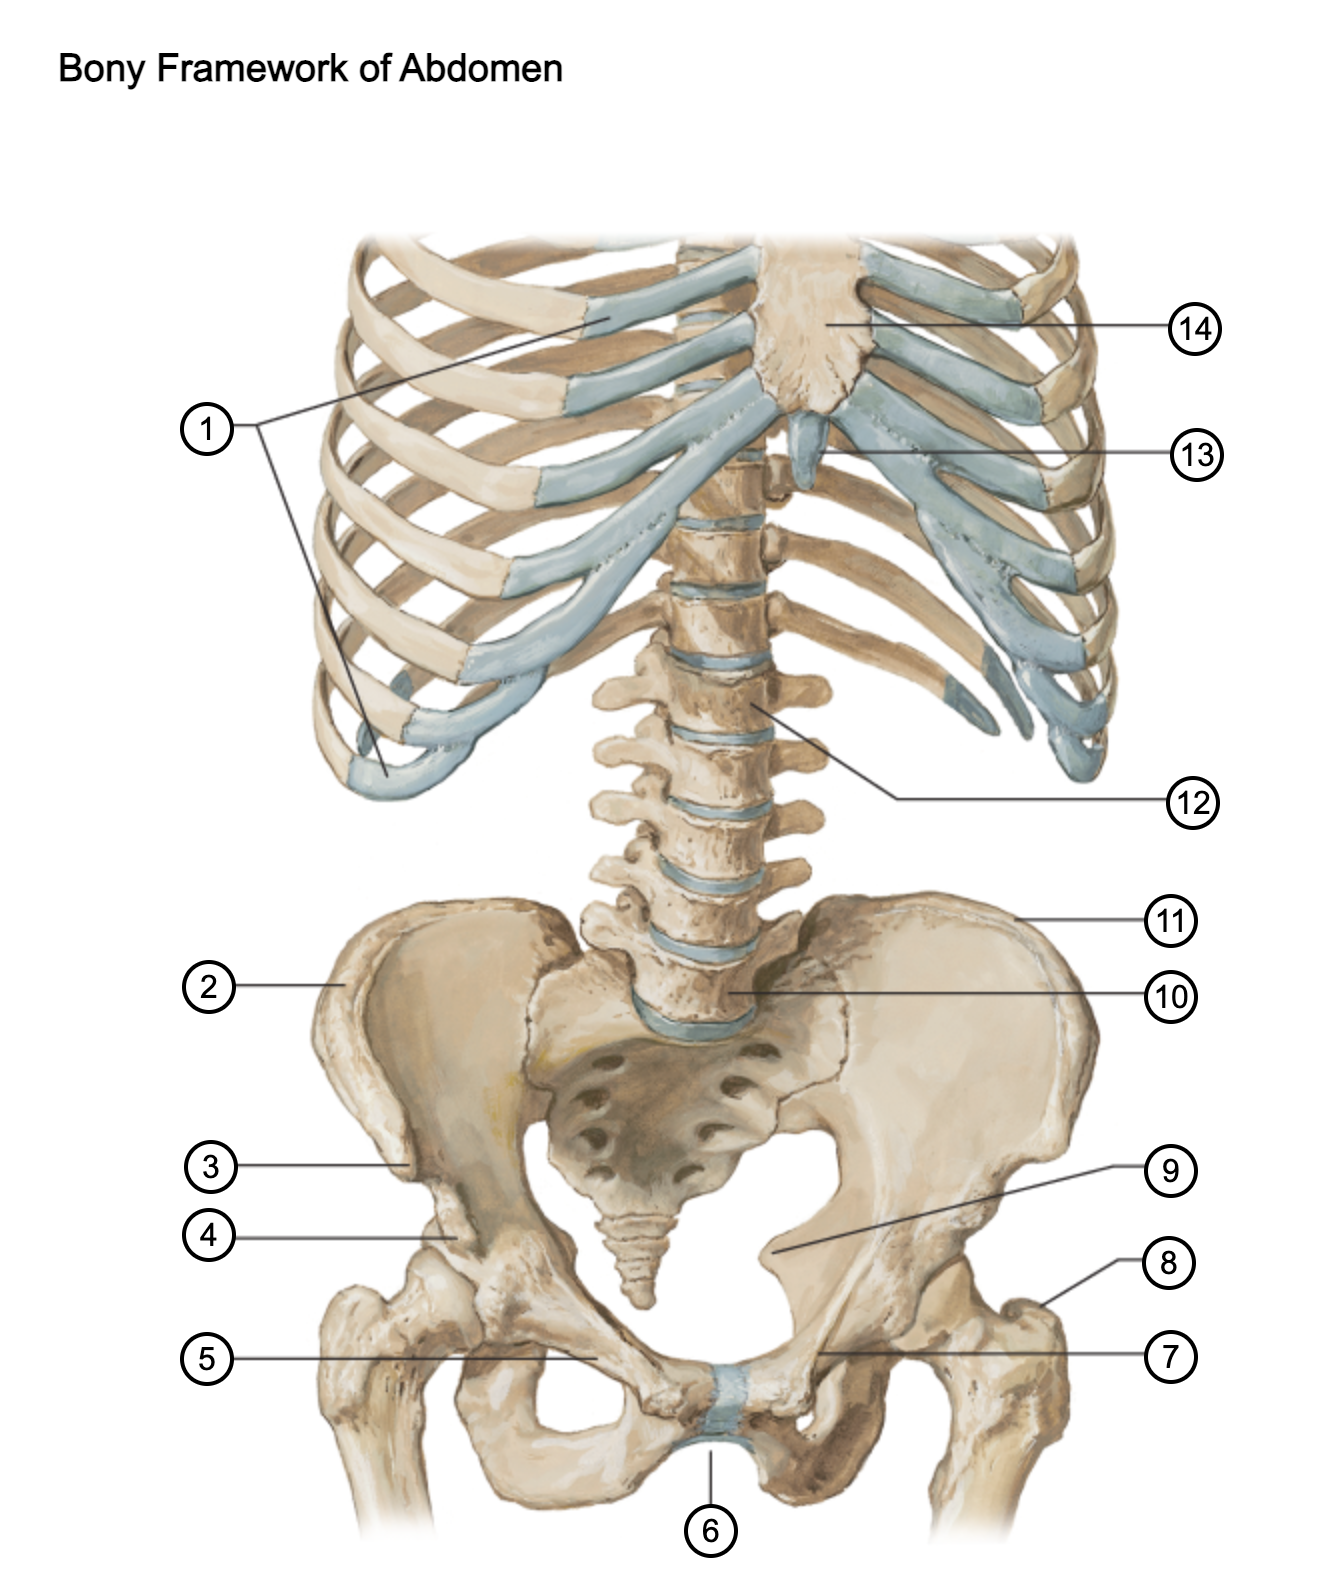

1

costal cartilages

2

iliac crest

3

anterior superior iliac spine

4

anterior inferior iliac spine

5

superior pubic ramus

6

pubic arch

7

pecten pubis

8

greater trochanter

9

ischial spine

10

L5 vertebra

11

iliac crest

12

L1 vertebra

13

xiphoid process

14

body of sternum